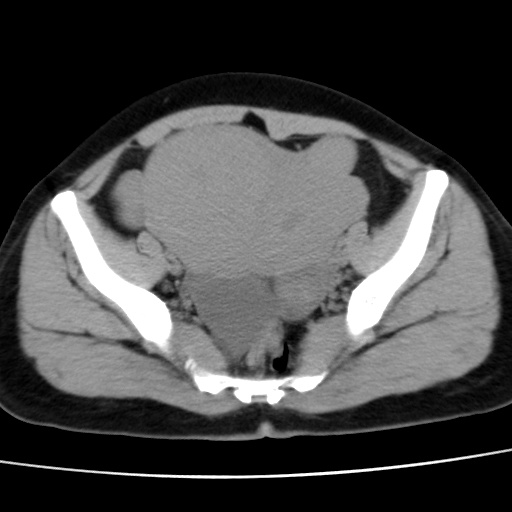

子宫多发肌瘤吗

多发性子宫肌瘤.

考虑多发子宫肌瘤,子宫直肠窝双囊性占位,另直肠周围脂肪密度增高,不知有何病史

支持考虑多发子宫肌瘤~!子宫直肠陷凹积液?

支持考虑多发子宫肌瘤~!子宫直肠陷凹积液!

子宫肌瘤,宫体部后方见液性密度影,是肠道还是子宫与直肠陷窝积液不好说,我觉得它的位置有点高

支持考虑多发子宫肌瘤!子宫直肠陷凹积液!

患者发热,而子宫直肠窝液性灶有明显边缘且局限且囊性,不除外为包裹性积液或脓肿

支持考虑多发子宫肌瘤,子宫直肠陷凹积液可能。

考虑多发子宫肌瘤

1)考虑子宫肌瘤可能性大。2)子宫后方囊性占位性病变,不排除卵巢囊肿可能。

考虑多发子宫肌瘤。子宫后方囊性占位性病变,不排除卵巢囊肿可能。